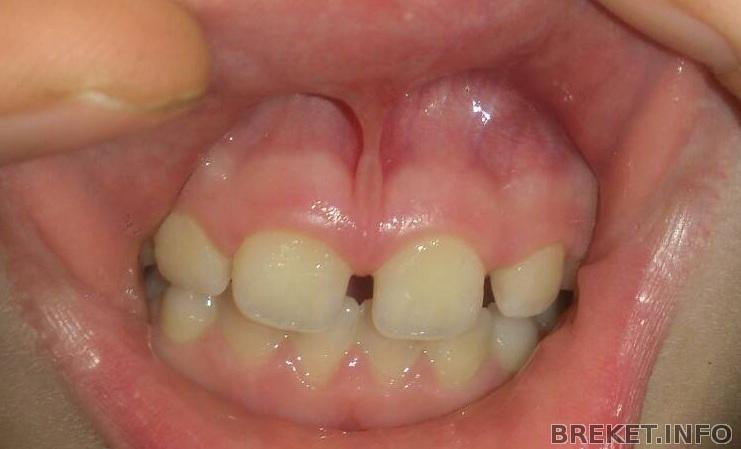

Здравствуйте, мы пришли к ортодонту с вопросом подрезать ли дочке уздечку верхней губы, чтоб убрать диастему, между верхними резцами (по направлению терапевта). Но врач сказал что его наша уздечка совсем не беспокоит, он видит проблему в прикусе, а конкретно в том что нижние зубы сильно высоко заходят за верхние. Им предложено было лечение: изготовление пластинки которая не даст смыкаться жевательным зубам и они через пол года подтянутся вверх и исправят низкий прикус (он его так назвал) Еще дополнительно пластинка сдвинет в кучу 4 верхние резца и изменит их наклон немного вовнутрь (Зачем? Зубы действительно не туда смотрят?).

Уже пора. Не стоит ждать. Тем паче раз прозвучало нижние зубы сильно высоко заходят за верхние...низкий прикус (он его так назвал) И на фото действительно так.

На самом деле этот прикус называется глубоким. И это проблема скелетная чаще всего (связана с челюстями). Вот здесь почитайте (я отвечал кому то недавно) http://breket.info/consult-doctor/1074491663 Отсюда вопрос: зачем ждать зубов если проблема не в них?